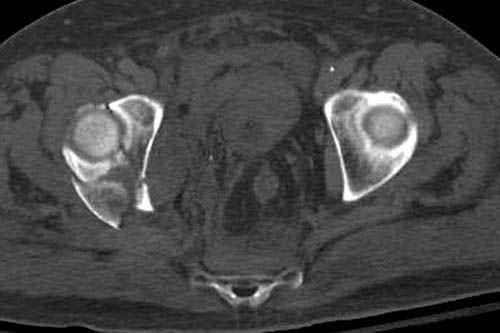

Дополнительно имеется перелом ацетабулума: задняя

колонна с полупоперечным переломом, и переломы костей лица.

На седьмой день зафиксирован перелом ацетабулума через задний доступ. Перед операцией для профилактики DVT, IVC фильтер, также получает Lovenox.

По снимку создается впечатление о высоком поперечном переломе, задней колонны, стенки; почему не пользовались *magic screw*?